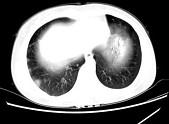

问题 女,24岁,HCG阳性,咯血2天,行胸部CT扫描如图,其最可能的诊断为 ( )

选项 A.转移性绒癌 B.肺部感染 C.肺结核 D.肺血管瘤 E.肺淋巴管肌瘤

答案 A